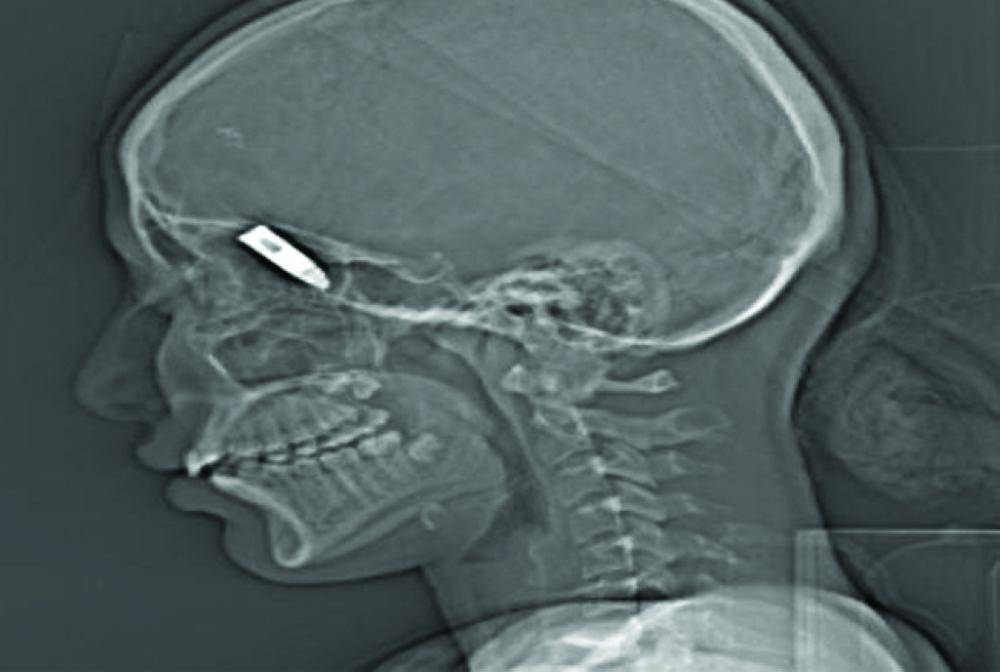

في حادثة سابقة أصيب رضيع يبلغ من العمر عامين ونصف العام بجروح خطيرة جراء سقوط طلقة نارية طائشة أطلقت في مناسبة زواج بقرية أبو حجر التابعة لمحافظة صامطة جنوب جازان، وفي أخرى نجح فريق طبي في مدينة الملك فهد الطبية، بقيادة استشاري جراحة الأطفال الدكتور عبدالوهاب الجباب، في استخراج عيار ناري استقرّ في ظهر طفل يبلغ من العمر 8 سنوات، كان العيار الناري الناجم عن إطلاق نار عشوائي قد استقر في ظهر الطفل لمسافة 5 سم من العمود الفقري، كما تمكّن فريق طبي بمدينة الملك فهد الطبية من إنقاذ حياة فتاة تعرّضت لإصابة بعيار ناري انطلق من إحدى مناسبات الأعراس بوادي الدواسر.

وكانت الفتاة برفقة والديها في إحدى الاستراحات المجاورة لموقع المناسبة، حيث أصابها العيار الناري واستقر في رأسها، ما استدعى نقلها على وجه السرعة للمستشفى.